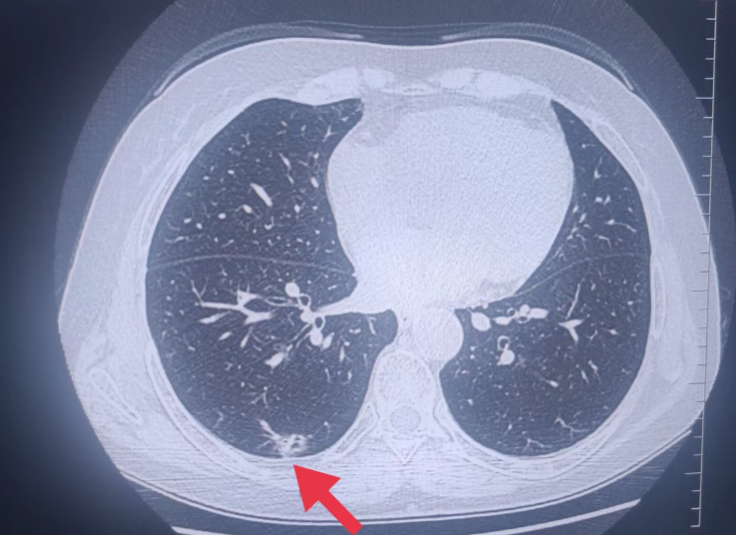

08**男士,68岁

2023年9月29日在邯郸仁泰北区体检,低剂量螺旋CT检查提示左肺下叶占位病变并远端肺不张,肿物大小约40X45mm(im247),左侧胸腔积液。诊断:左肺下叶占位病变并远端肺不张,左侧胸腔积液,当日通知客户到三甲医院进一步检查,2023年10月3日跟踪回访,客户反馈已住院,准备手术治疗。